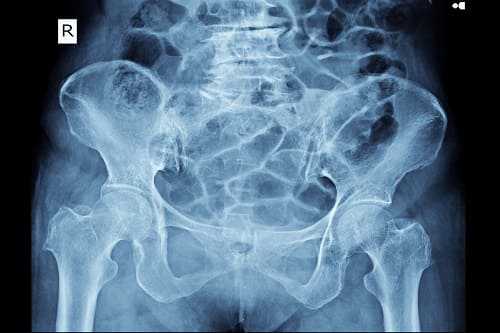

- Инструментальные обследования. Оценка состояния мышц нижней конечности и проводимости седалищного нерва осуществляется при помощи электронейрографии. По показаниям для выявления тазовой асимметрии, онкопатологии, травматических повреждений проводится рентгенография костей таза, КТ и МРТ позвоночника, УЗИ органов малого таза.

Последнее время для оценки состояния ствола нерва и окружающих его анатомических образований используют методику УЗИ, способную дать информацию о наличии опухоли нерва, его сдавлении, дегенеративных изменениях и т. п. Определение генеза невропатии может проводиться с использованием рентгенографии позвоночника (в некоторых случаях — КТ или МРТ позвоночника), рентгенографии таза, УЗИ малого таза, УЗИ и рентгенографии тазобедренного сустава, КТ сустава, анализа сахара крови и пр.